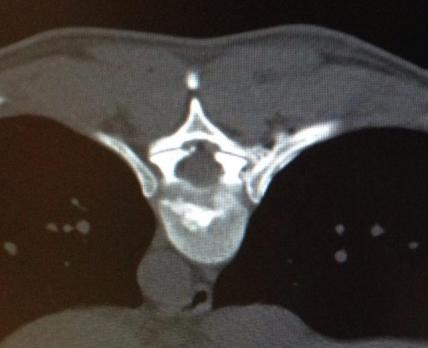

Atrophy of a facette

2 thin needles are guided to the joint space

The surgeon will insert a very small needle into the painful joint and will be guided by an X-Ray control. With the help of the needle where a small laser fiber can be inserted the surgeon can now desolate the nerve which causes the pain.